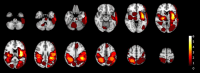

Methods: Using a simulation approach, we analyzed magnetic resonance imaging (MRI) scans of stroke-suspected patients within 4.5 h of symptom onset to assess TCCS and NIRS for identifying imaging-based IVT contraindications. Our study included both primary and sensitivity analyses, each employing conservative and optimistic scenarios. The primary analysis integrated clinical information from the emergency department, while the sensitivity analysis evaluated overall performance across all patients, regardless of clinical information. The conservative scenario defined TCCS detecting acute deep-brain hemorrhages or tumors >20 mm from scalp surface or > 10 mL in volume or causing >4 mm midline-shift, while NIRS was defined detecting them <20 mm from scalp surface with a volume > 3.5 mL. The optimistic scenario defined TCCS detecting intracranial or subarachnoid acute/subacute hematoma or tumors >20 mm from scalp surface or > 5 mL in volume or causing >2 mm midline-shift, while NIRS was defined detecting them <35 mm from the scalp surface with volume > 3.5 mL.

Results: We assessed 1,089 consecutive patients undergoing acute MRI, identifying 69 with imaging-based IVT contraindications, of which 40 had additional non-imaging contraindications. In the primary analysis, among those 29 patients without non-imaging-based contraindications, TCCS/NIRS would have detected 15 of 25 ICH and 3 of 4 malignant tumors in the conservative scenario. In the optimistic scenario, 18 of 25 ICH and all malignant tumors would have been detected. In the sensitivity analyses, the conservative scenario would have detected 30 of 52 ICH and 8 of 17 malignant tumors, while the optimistic scenario would have identified 37 of 52 ICH and 12 of 17 malignant tumors.